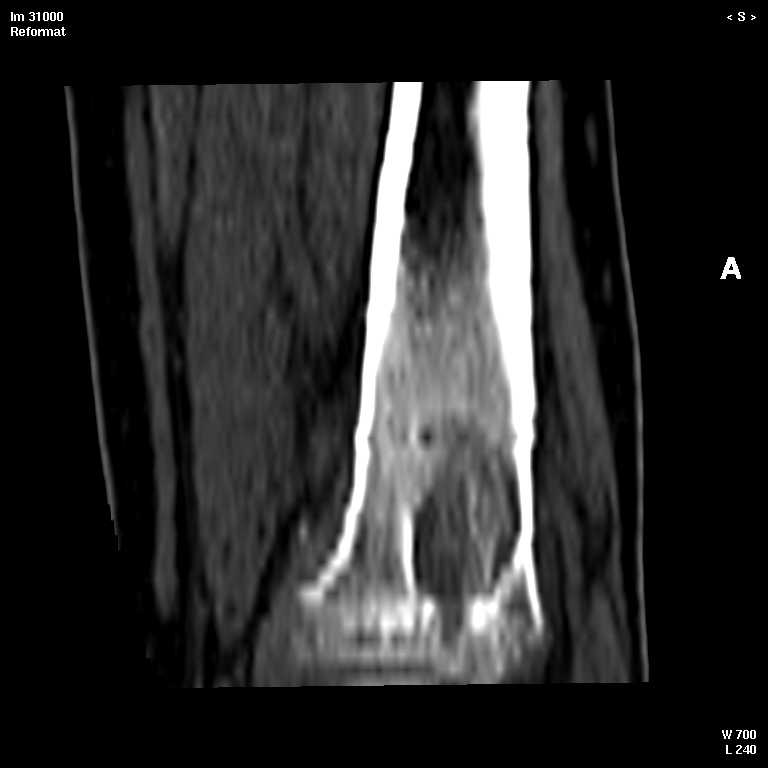

В обсуждении темы возникла необходимость дополнительных данных.

КТ изображения передаю на мой взгляд самые демонстративные. Их любезно записал коллега,

проводивший исследование в другом городе.